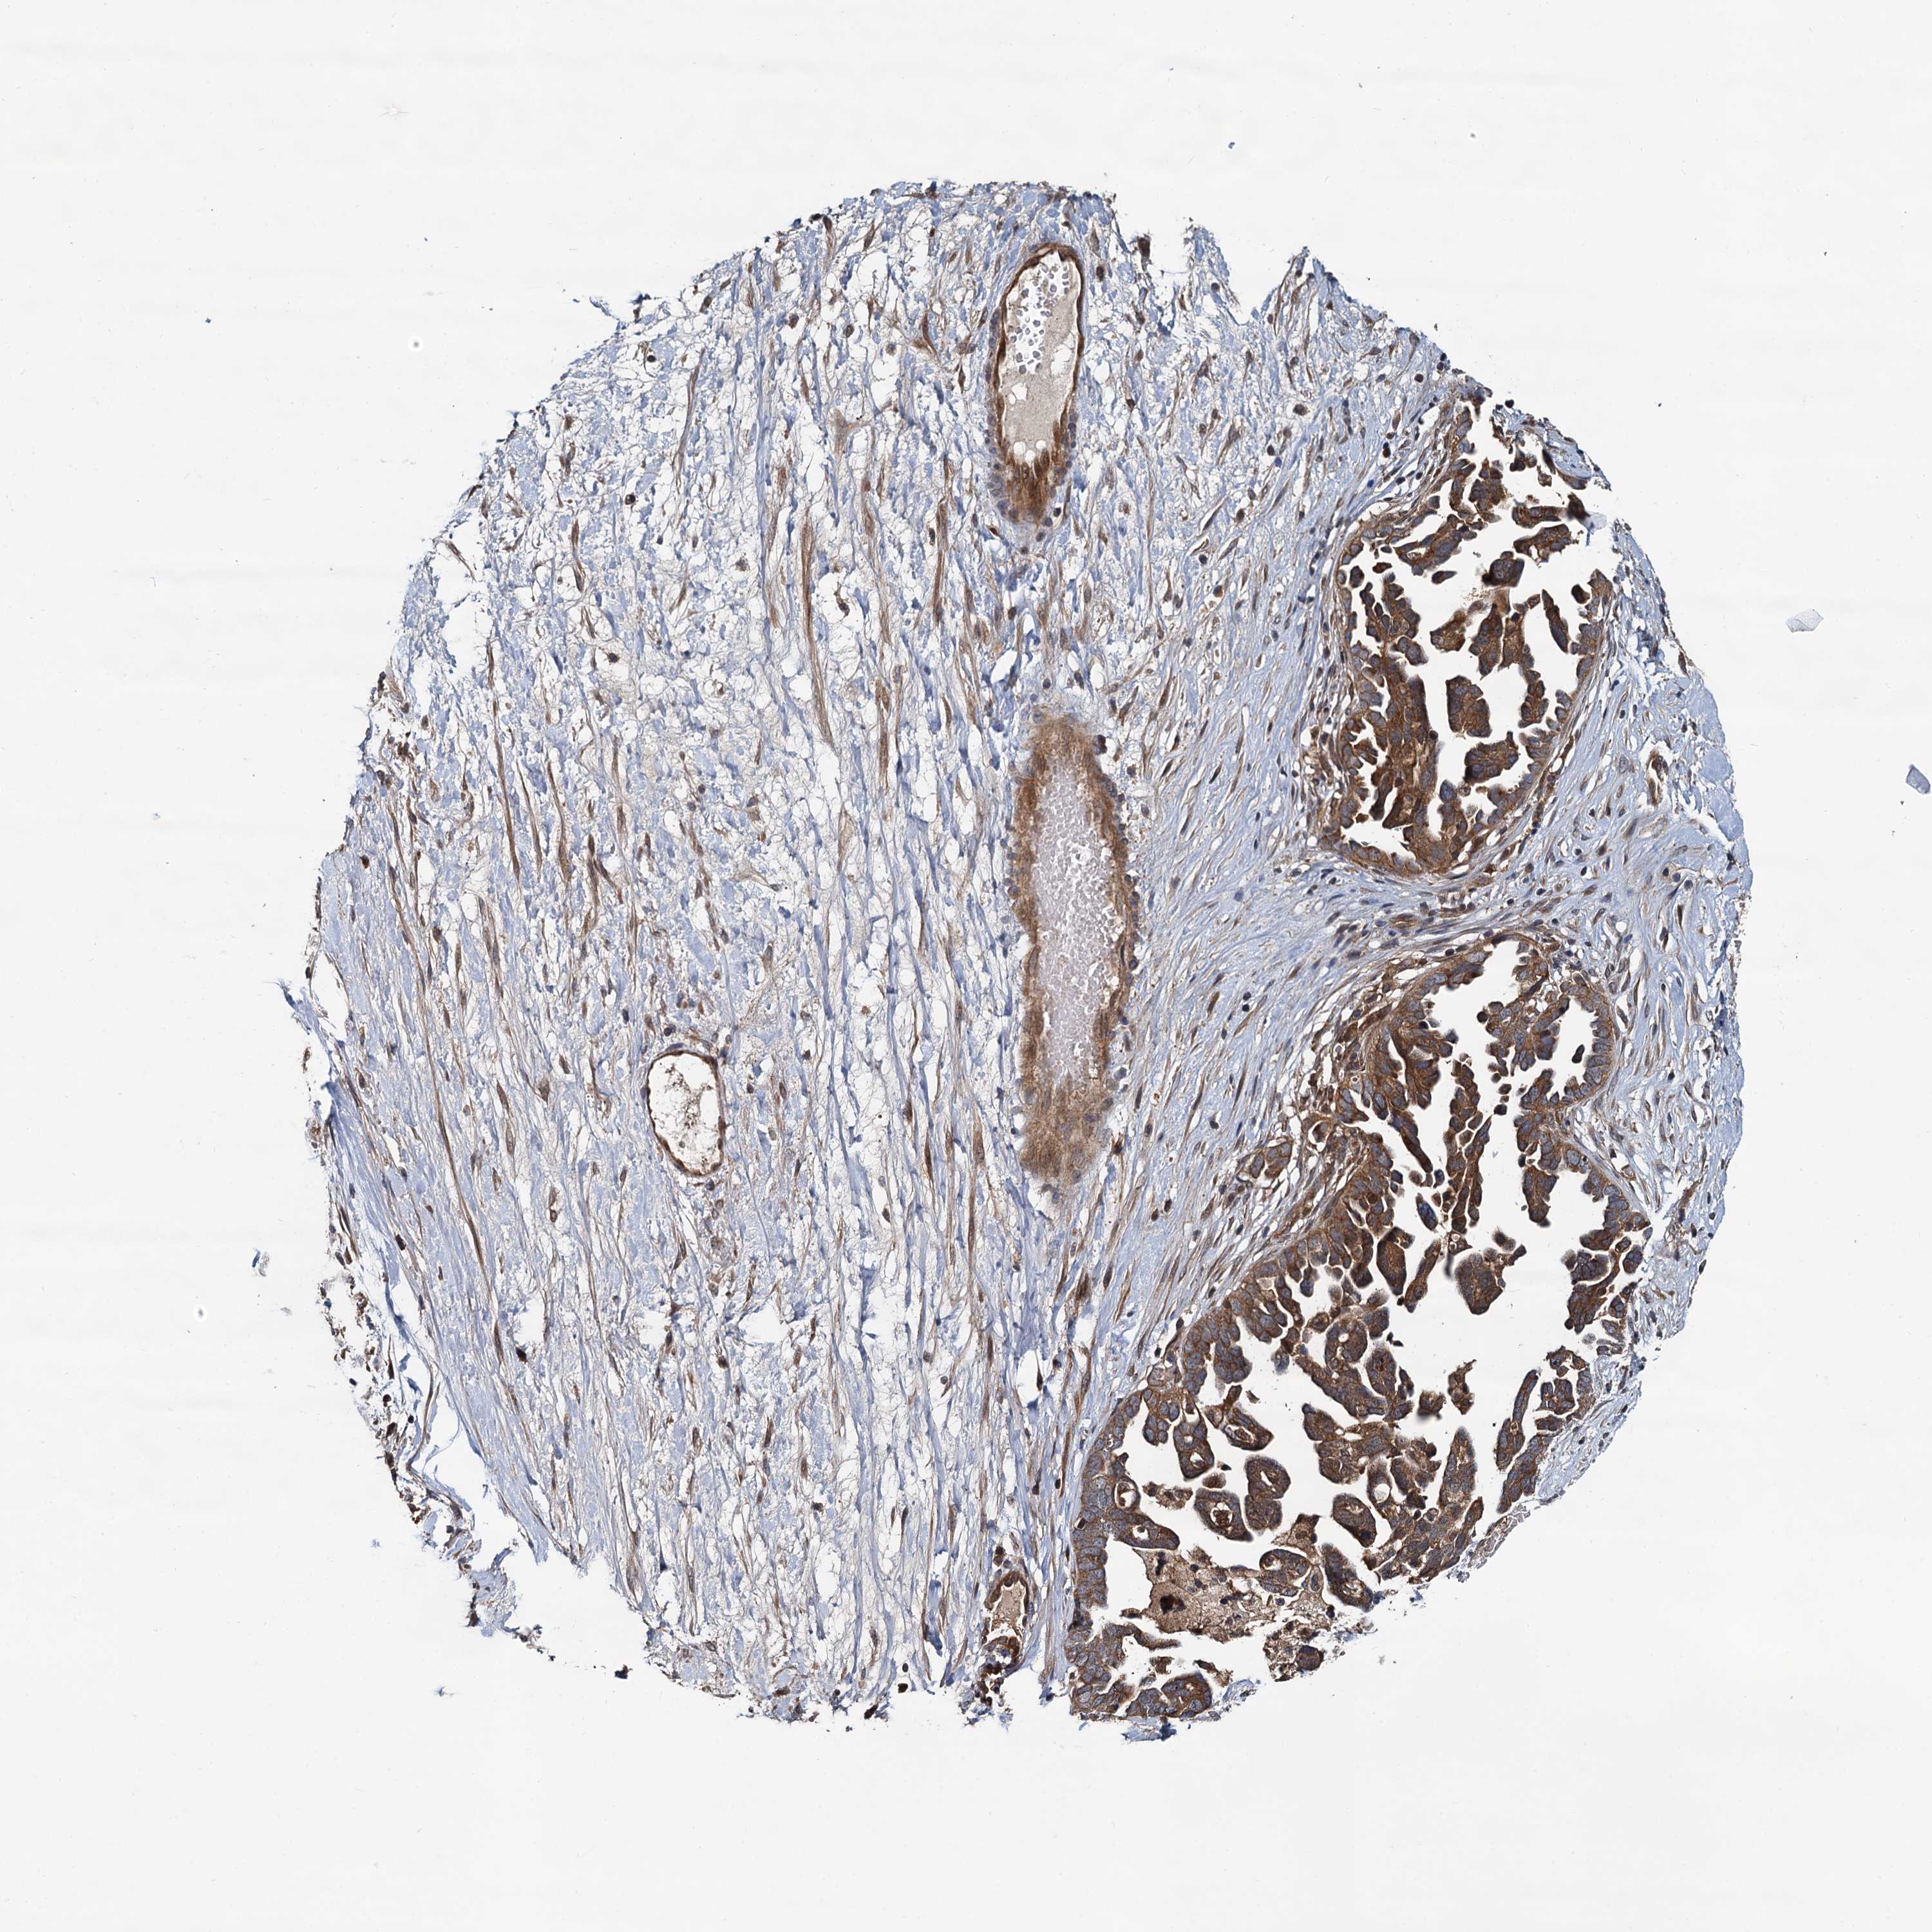

OVARIAN CANCER - Protein expressioni

A mouse-over function shows sample information and annotation data. Click on an image to view it in a full screen mode. Samples can be filtered based on level of antibody staining by selecting one or several of the following categories: high, medium, low and not detected. The assay and annotation is described here.

Note that samples used for immunohistochemistry by the Human Protein Atlas do not correspond to samples in the TCGA dataset.

Antibody stainingi

Antibody staining in the annotated cell types in the current human tissue is reported as not detected, low, medium, or high, based on conventional immunohistochemistry profiling in selected tissues. This score is based on the combination of the staining intensity and fraction of stained cells.

Each image is clickable and will lead to virtual microscopy that enables deeper exploration of all samples and also displays staining intensity scores, fraction scores and subcellular localization as well as patient and tissue information for each sample.

Antibody HPA039371

Antibody HPA040174

Staining

High

Cystadenocarcinoma, serous, NOS

Carcinoma, endometroid

Cystadenocarcinoma, mucinous, NOS

Carcinoma, NOS